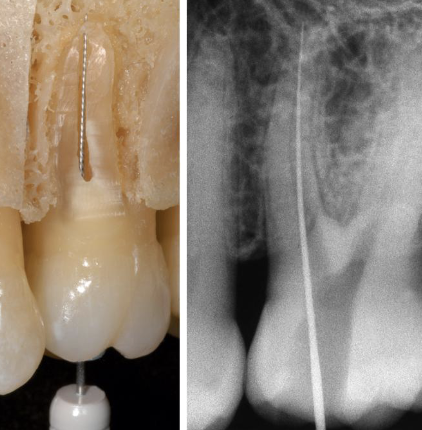

Correct working length is critical to meet the goals of biomechanical and chemomechanic preparation. What is working length?

From the coronal to the apical extent of the root canal system

Working length is the distance from

A coronal reference point tot he point at which canal preparation and obturation should terminate

For the working length, if there is difficulty viewing the file, you can use

A 15K file or larger

To determine working length, this helps clinically along with radiographic WL

Combination of apex locator measurements + radiographic WL